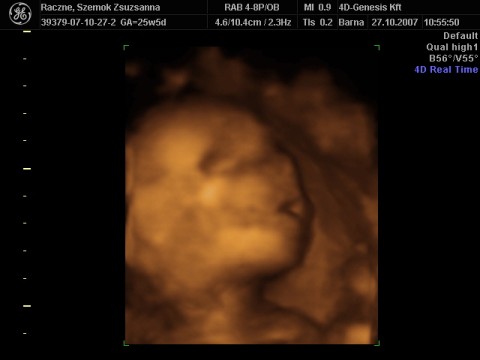

Zsu,

még jó , hogy jók lesznek a képek.

Remélem jobban látszik az én kis szerelmem!!!!